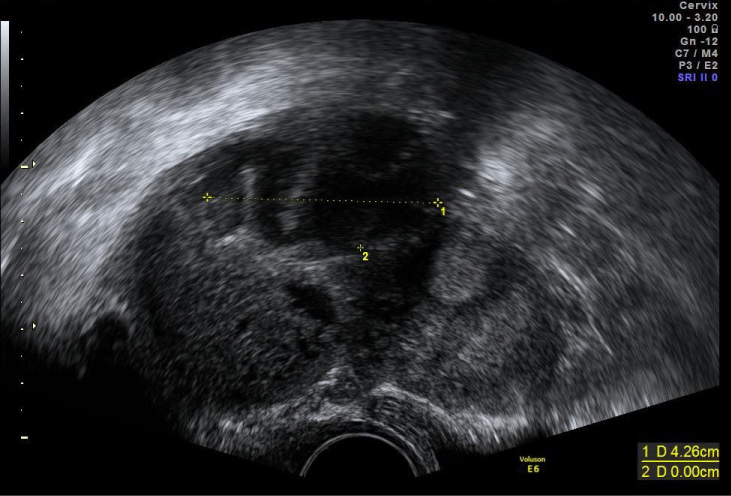

Transvaginal ultrasound scan revealed a thickened double layer endometrium with 17 mm but empty uterine cavity, together with a heterogeneous adnexal mass at the right tube with 6 cm of largest diameter and a small amount of free fluid at the Douglas Pouch (Figure 1).

Figure 1: Transvaginal ultrasound scan at admission showing adnexal heterogeneous mass suggestive of tubo-ovarian abscess. View Figure 1

At discharge, the patient was fully clinically recovered, with normal inflammatory values. At ultrasound, there was the same heterogeneous right adnexal mass with four cm of largest diameter (Figure 2) and no fluid at the Douglas Pouch and an intrauterine gestational sac with yolk sac (Figure 3).

Figure 2: Transvaginal ultrasound scan showing tubo-ovarian abscess after 14 days of treatment. View Figure 2